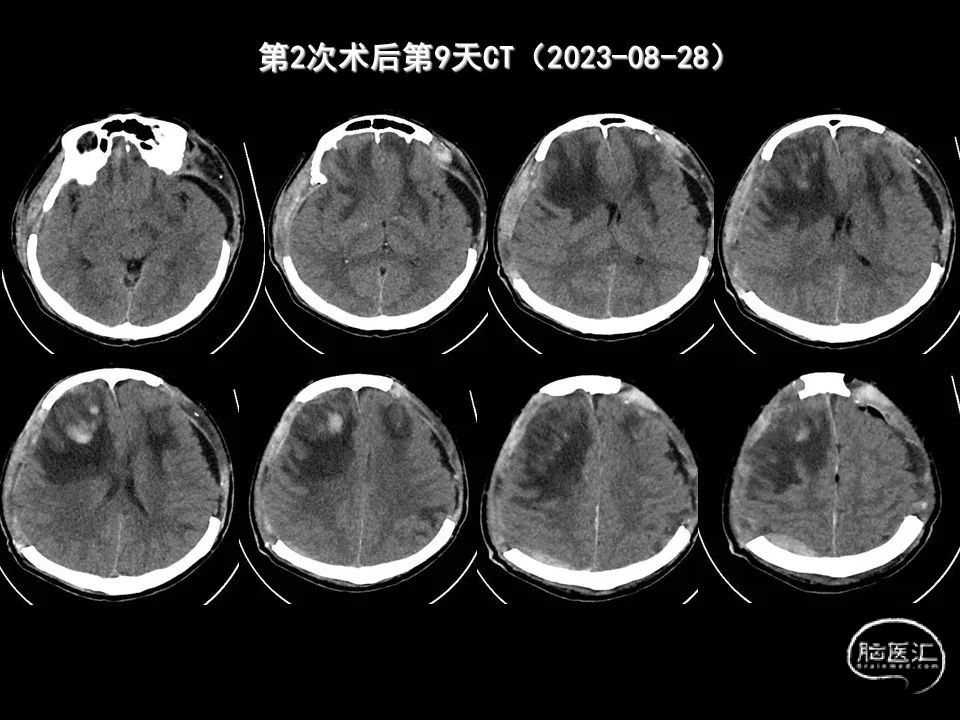

今天为大家分享的是《监测有道丨颅脑创伤-神经重症周刊》第338期,由海南省人民医院朱蔚林教授带来的:2例脑出血微创手术,欢迎阅读、分享。